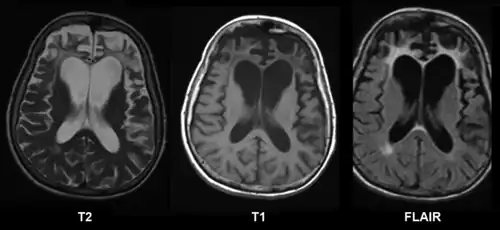

A range of neuropsychological tests are available for clarifying the nature and extent of frontal lobe dysfunction. For example, concept formation and ability to shift mental sets can be measured with the Wisconsin Card Sorting Test, planning can be assessed with the Mazes subtest of the WISC.[3] Frontotemporal dementia shows up as atrophy of the frontal cortex on MRI.[20] Frontal impairment due to head injuries, tumours or cerebrovascular disease will also appear on brain imaging.[4]